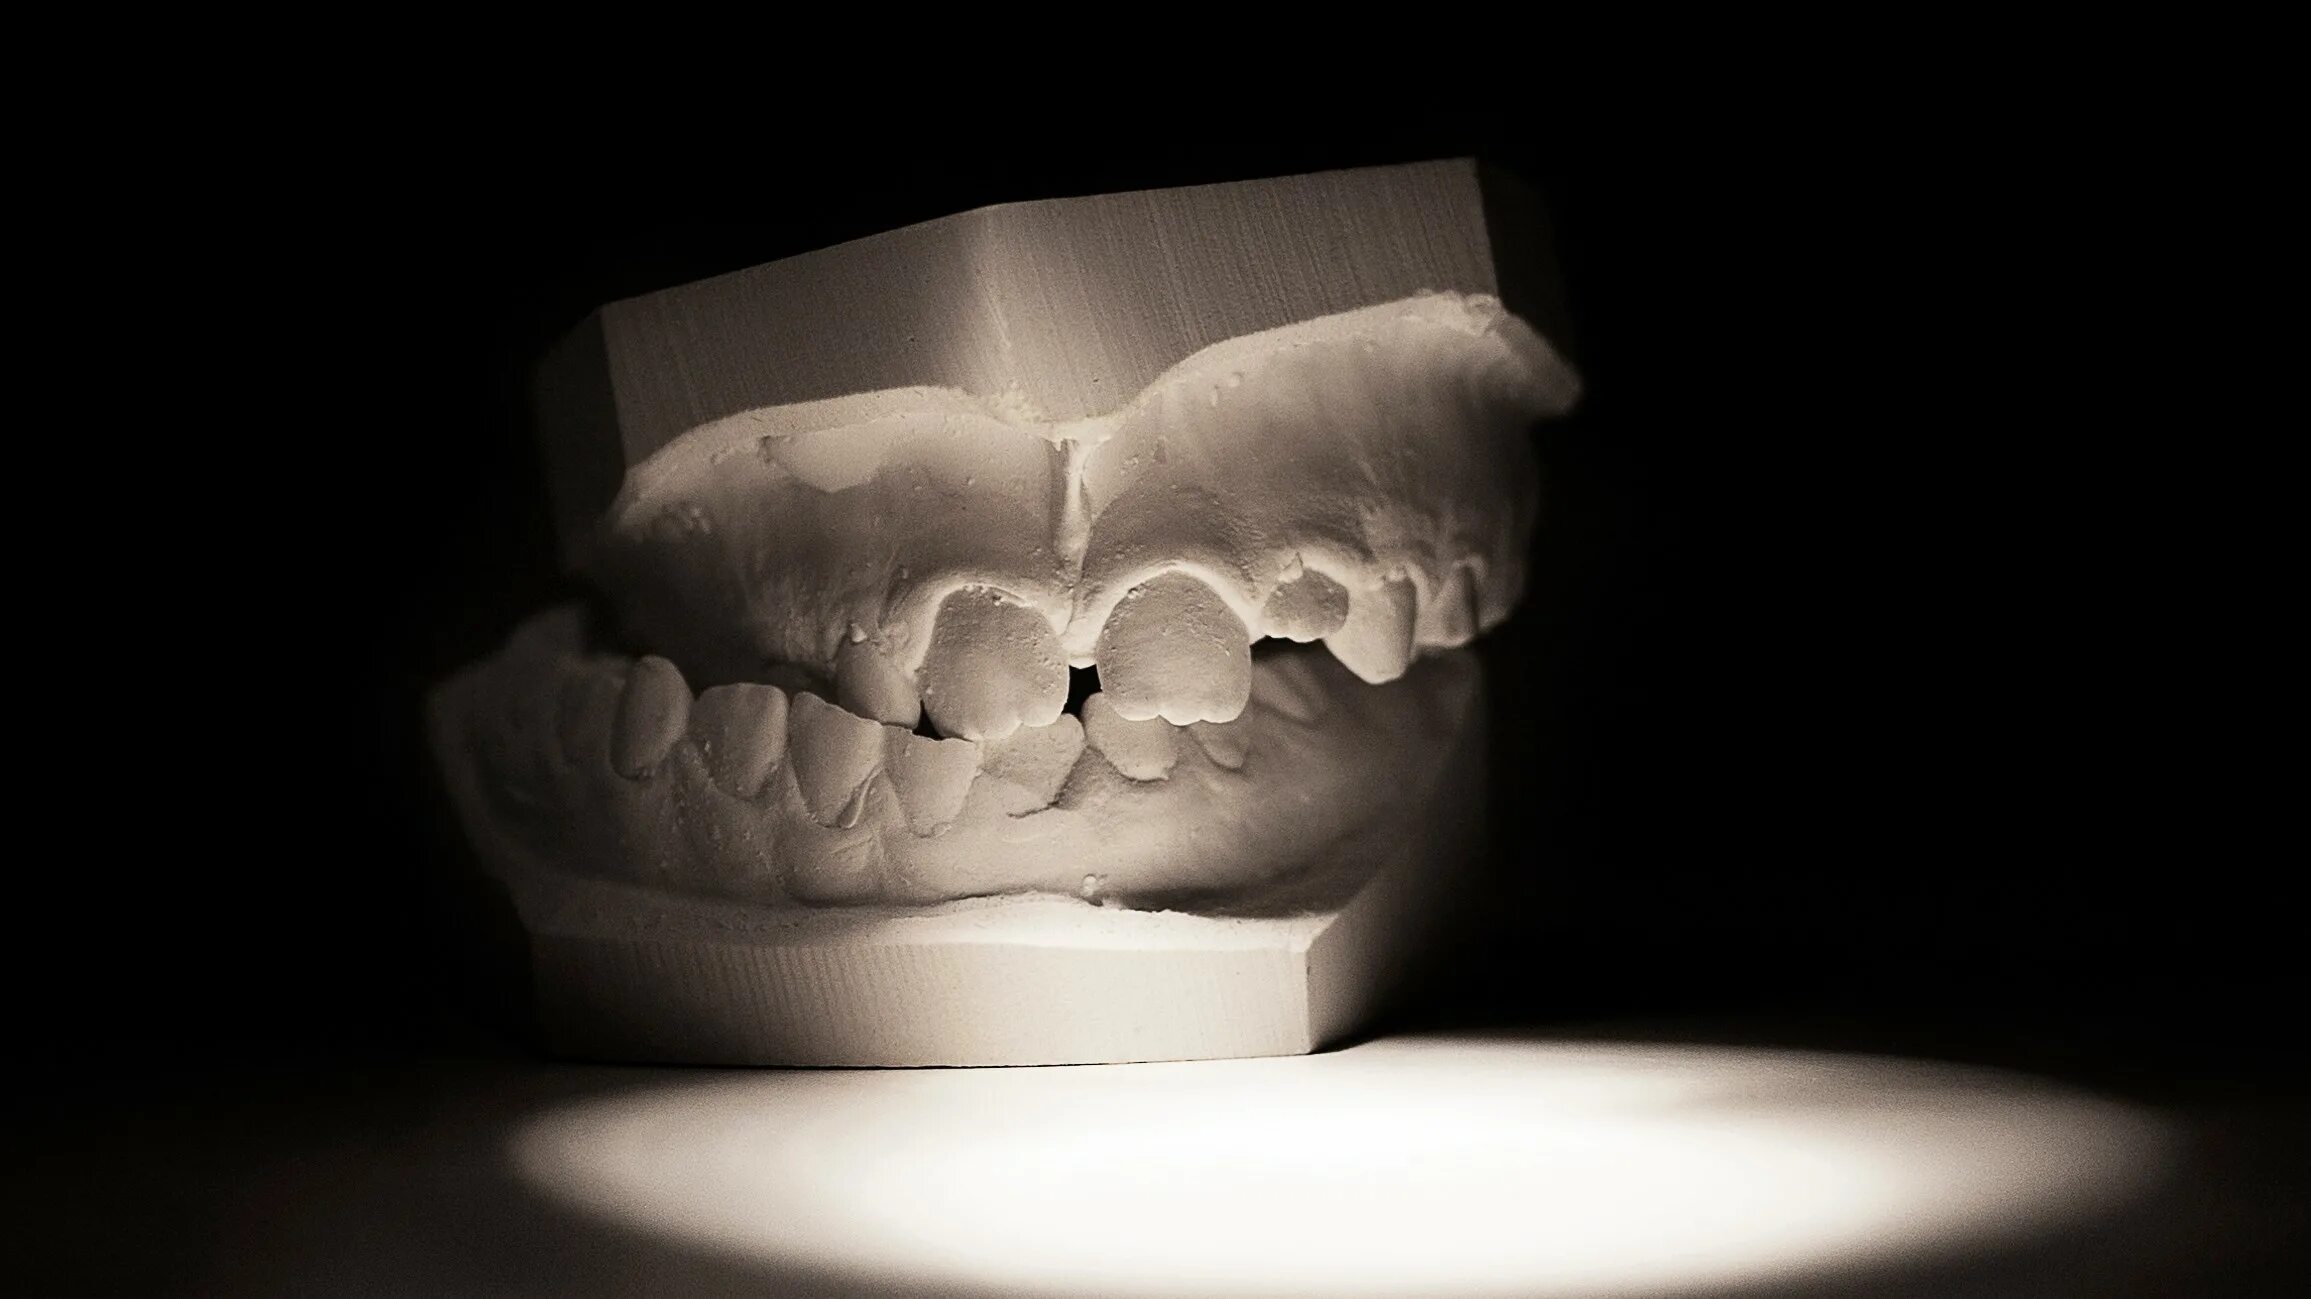

Что делать если заклинило челюсть